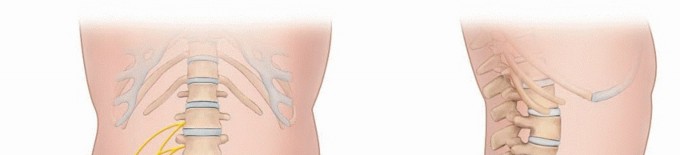

DEFINITION Care of peripheral nerve problems requires knowledge and understanding of nerve pathology, anatomi…